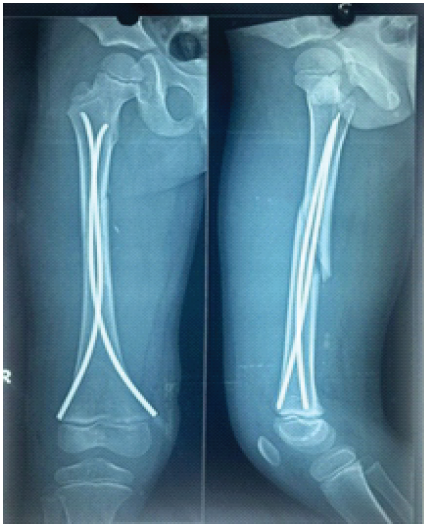

Post-operatively, patients were followed for 6 months with evaluations at 6, 12, and 24 weeks. Partial weight bearing was started at 6 weeks and gradually increased to full weight bearing once radiographic evidence of fracture union was observed on anteroposterior and lateral X-rays. During follow-up, patients were assessed for the time to fracture union, the occurrence of complications, such as superficial or deep infections, implant prominence or migration, fracture angulation, loss of reduction, fracture collapse, limb shortening, and range of motion. In addition, at the past follow-up, an orthoroentgenogram (scanogram) was performed to check whether there was limb length discrepancy (LLD). Pain, malalignment, LLD, and complications were reported and classified according to Flynn’s criteria. Ethical clearance was taken from the institute. In the image, Fig. 1 is showing mid 1/3rd shaft of femur fracture. Fig. 2 & 3 is showing immediate post-operative X-ray. Fig. 4 shows 2 years of follow-up, and Fig. 5 shows the X-ray after hardware extraction.

Figure 3: Immediate post-X-ray.